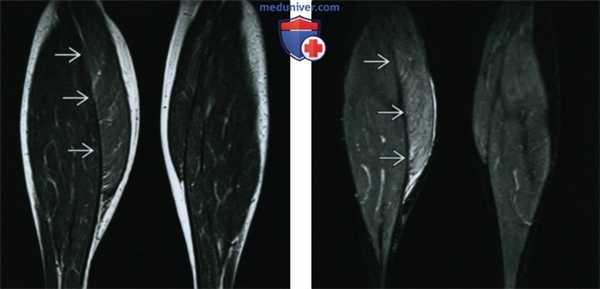

(Слева) МРТ Т1ВИ, корональный срез: при визуализации обеих нижних конечностей определяется диффузное увеличение размеров правой икроножной мышцы. На этой томограмме усилена интенсивность внутримышечного сигнала, обусловленная увеличением объема внутримышечной жировой ткани. Такая картина характерна для псевдогипертрофии.

(Справа) MPT STIR, корональный срез: у этого же пациента определяется повышение интенсивности внутримышечного сигнала в правой икроножной мышце. Такие отечные изменения наблюдаются как при истинной гипертрофии, так и при псевдогипертрофии.